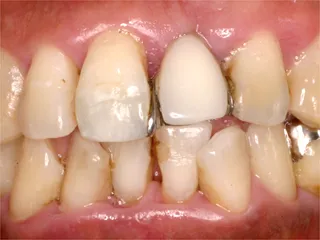

| 自費ブリッジ |

保険のブリッジ

通常のブリッジは 強度を維持するため大きくなります メタルボンドは 適正なサイズで色も自然です ■長所 ・金属が見えない ■短所 ・前後の歯を削り犠牲にする ・高い |